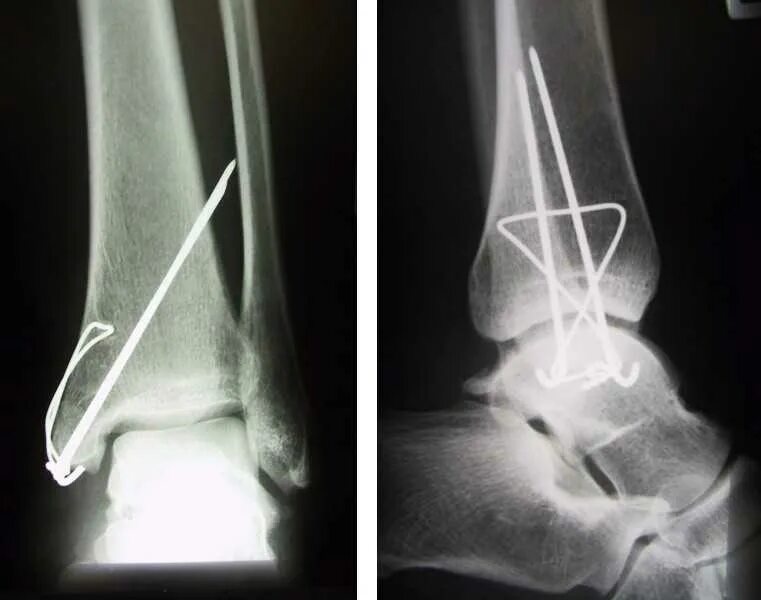

После остеосинтеза лодыжек